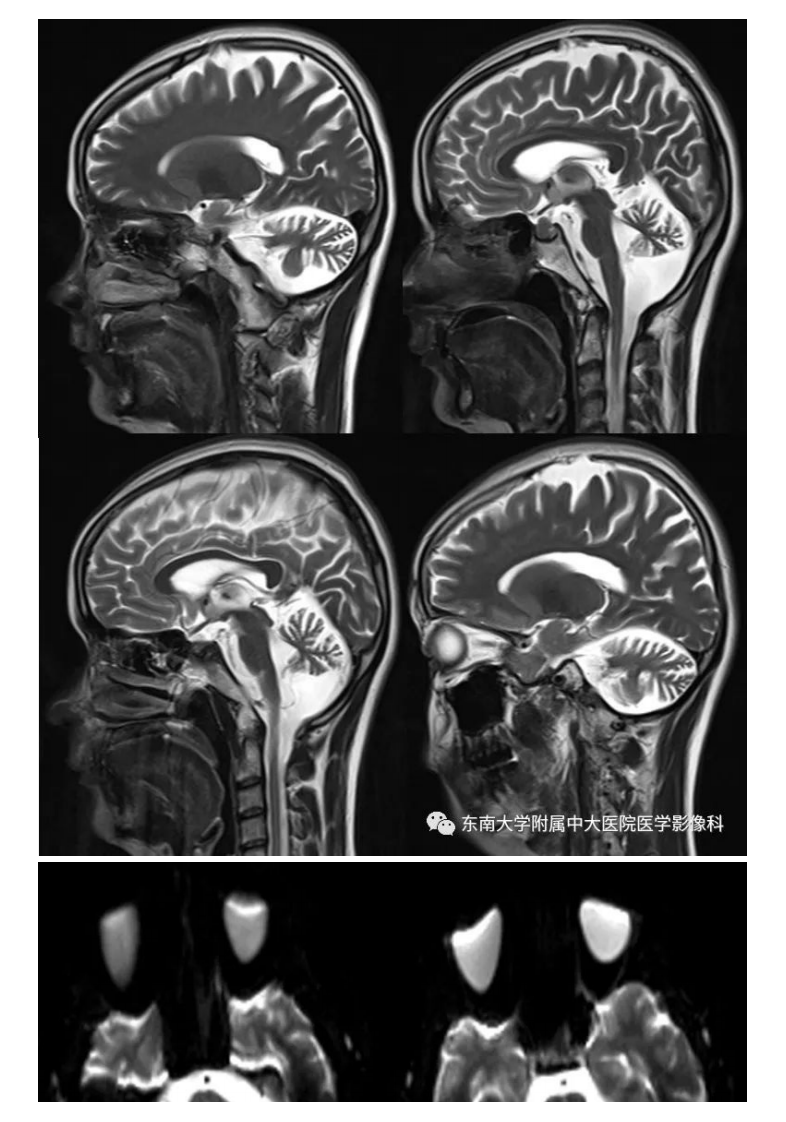

20200928_2【晨读结果公布】2020.09.28神经系统疾病——脊髓小脑性共济失调(病例1).pdf